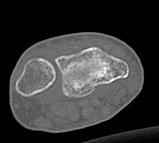

Уважаемые коллеги.Прошу обсудить случай лечения перелома дистального метаэпифиза лучевой кости. Ситуация скандальная и крайне неблагоприятная. Больная с патологической обстоятельностью мышления, склонностью к сутяжничеству, патологическими умозаключениями, не поддающимися коррекции (см. психиатрию, правда офиц. диагноза нет). В данном случае есть ряд ошибок с нашей стороны, прежде всего в отношении качества ведения документации (за что получил административное взыскание, по делом мне дураку). В остальном- придерживались в лечении подхода классический советской школы. Так как умную операцию…… сами знаете… 15.12- перелом луча в Москве. Там же репозиция, гипс. Дальнейшее лечение у нас в ЦРБ. 20.12.- вторичное смещение в гипсе21.12- под внутривенным наркозом- репозиция, гипсовая лонгета. Дальше начинается самое интересное. После репозиции больная заявила, что я (репозицию делал я) порвал ей все связки в суставе, посинел у нее 5 палец, якобы я за него тянул и т. д. На самом деле на 2 сутки после репозиции рука немного отекла и было незначительное сдавление гипсом, который был ослаблен. Дальнейшее лечение консервативное. Через 6 недель- гипс снят, назначено ЛФК. Пациентка крайне недовольна. Говорит, что на снимке у нее выступает кость, я ей сломал руку и.т.д. В общем началось. Пациентка прочитала в интернете наверное все, что есть по данной травме.По заключениями рентгенологов и консультанта из КДЦ областной больницы - стояние отломков допустимое. Объективно говоря- снижена высота лучевой кости, диастаз лучелоктевого сочленения, и не сросся шиловидный отросток. однако на РКТ при сравнении с другой стороной- разница незначительная. Дальше в одной из больниц нашей области и одной из больниц Москвы (вроде бы КГБ 53) врачи сказали, что репозиция сделана плохо. Нужна операция (восстановить длину лучевой кости), даже один из них предложил РЕДРЕССАЦИЮ (хи-хи) с наложением аппарата Илизарова. Что это для данной больной- радость неописанная. (см. описание психического статуса). Ничем другим, кроме зарабатывания дешевого авторитета объяснить данный факт не могу.Кстати, у больной еще нейропатия локтевого нерва.Для разрешения конфликта больная направлена на консультацию в ЦИТО на 03.03.11.

2. По сравнению и без ! втор смещение незначительное.НЕТ НИКАКОЙ ,,локтевой косорукости,,маделунгов . но имеется смещение совести у врачей КГБ 35--НЕТ ЗДОРОВЫХ, есть только недообследованные ! Этому смещению аппарат внешней фиксации не поможет .Психопаткам в менопаузе да весной только этого и надо чуть толкнули и поехало .

2.Укорочение лучевой кости и лучелоктевой диастаз невелики,но отрицать их клиническую значимость весьма сложно.